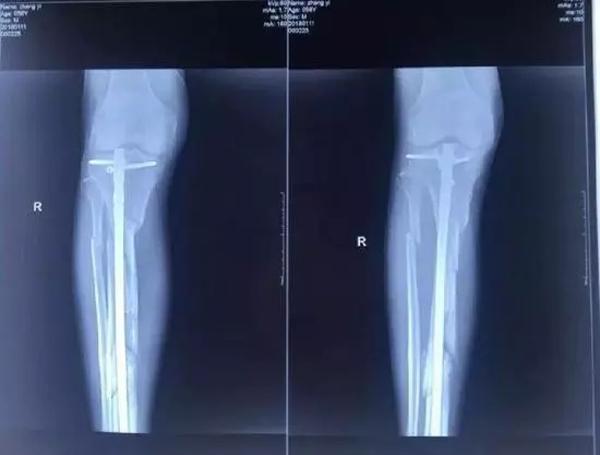

他興辦的廊坊市城南骨科醫院發展得越來越好,引起了原本是小股東的楊玉忠對醫院的覬覦。股東如果想要擴大股權,有許多正常的途徑,用合理合法的方式完全可以實現。但楊玉忠卻采取了最直接卻也最暴力的方式,不斷用欺騙、騷擾、干預人事等方式排擠張毅,使他在專心看病的同時,疲于應付,心理壓力極大,甚至在2017年10月18日,張毅被四名駕駛無牌豪華越野車的黑衣人打斷腿骨。即使是如此,當地黑惡勢力依然沒有放過張毅,不僅舊醫院被掏空占據,新醫院也無法開張,200多醫護人員面臨衣食無著的困境。雖多方求助,對方依然逍遙法外,最終逼死了張毅。

資料圖